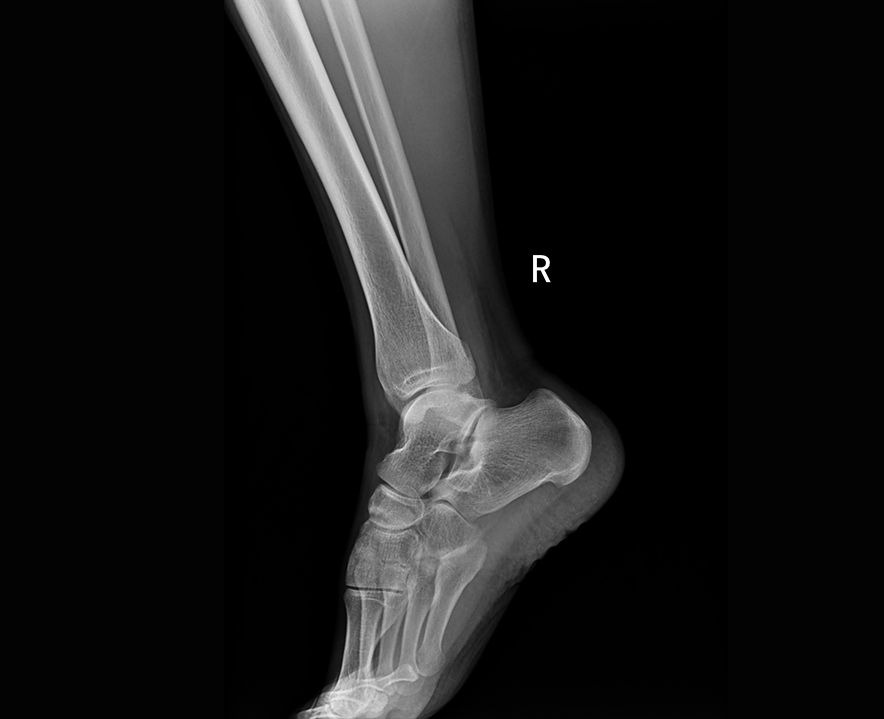

臨床圖像